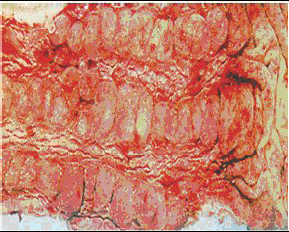

Диаррея наблюдается почти у 50% больных, длительно находящихся в критических состояниях. Выделяют 4 основных типа поносов с различными механизмами развития (осмотическая, секреторная, экссудативная и моторная /двигательная/ диарея). Диарея, возникающая в течение нескольких дней после эпизода остановки сердца или выраженной артериальной гипотензии, может быть признаком ишемического повреждения слизистой оболочки в результате невосстанов- ления кровотока [30,62,71]. Осмотическая диарея. Потребление плохо абсорбируемых веществ обусловливает повышение осмолярности кишечного содержимого, торможение абсорбции воды, выход жидкости в просвет кишечника, что в итоге приводит к жидким испражнениям. Наиболее частые причины - погрешности в проведении зондового энтерального питания (12-25% от всех случаев поноса). В генезе вызванной зондовым кормлением осмотической диареи выделяют несколько провоцирующих факторов: гиперосмо- лярность или высокое содержание липидов; введение питательных растворов со скоростью ›50 мл/час либо в тонкую кишку; атрофия слизистой оболочки тонкой кишки; гипоальбуминемия. Ведущее значение в возникновении диареи придают повышенной осмотической концентрации питательных растворов, хотя на практике это не всегда достаточно очевидно. В некоторых случаях причиной диареи могут быть гиперосмотические растворы электролитов и лекарственных средств. Слизистая оболочка тонкой кишки претерпевает дегенеративные изменения (атрофия слизистой оболочки) при прекращении питания (естественным образом) на несколько дней. Часть поверхности кишки, необходимой для всасывания питательных веществ, теряется в результате нарушения абсорбции (синдром мальабсорбции) и осмотической диареи. Дегенеративные изменения в слизистой оболочке появляются и при парентеральном питании, причем их причиной считают отсутствие питательных веществ в просвете кишечника Атрофия слизистой оболочки также служит причиной диареи, возникающей при возобновлении естественного или зондового питания после длительного «отдыха» кишечника [34]. Гипоальбуминемия приводит к снижению коллоидно-осмотического давления плазмы крови, вследствие чего жидкость выходит из капилляров в просвет кишечника. Это также позволяет объяснить связь между гипоальбуминемией и диареей, вызванной зондовым питанием [28,32]. Секреторная диарея. В тонкой кишке в нормальных условиях секре- тируется до 9 л насыщенной электролитами жидкости, большая часть которой всасывается, еще не доходя до толстой кишки. Любой процесс, сопровождающийся гиперсекрецией при неизмененной абсорбции, приводит к секреторной диарее. Наиболее частой ее причиной является применение различных препаратов (антибиотиков. теофилли- на, слабительных средств). Нерациональное назначение антибиотиков является основной причиной наступления поноса (у 20-50% больных с диареей). Практически любой антибиотик способен вызвать диарею, кроме ванкомицина и, возможно, аминогликозидов. Частота обнаружения это-го осложнения в ходе проведения антибиотикоте- рапии увеличилась за последнее годы в 5 раз [82]. Большинство случаев диареи, как правило, ассоциированы с прямым действием антимикробных препаратов на двигательную активность тонкого кишечника, уменьшением ферментации сахаров в ЖКТ, выраженным повреждением кишечной стенки. 15%-25% поносов, обусловленных приемом антибиотиков, связаны с дисбактериозом. В настоящее время основным возбудителем диареи,обусловленной применением антибиотиков, считают Clostridium difficile - кишечный микроорганизм, способный интенсивно размножаться при подавлении препаратами обычной (сапрофитной) микрофлоры кишечника. Этот микроорганизм продуцирует цитотоксин, который повреждает слизистую оболочку толстой кишки. Clostridium difficile легко передается через зараженные предметы (например, туалетные принадлежности) или руки медицинского персонала) [3,13,38]. Экссудативная диарея возникает в результате повреждения слизистой оболочки кишечника с последующим выходом белков и крови в просвет кишки. Наиболее частые причины - панкреатит, псев-домембранозный энтероколит (рис. 6), ишемия тонкой кишки. Моторная (двигательная) диарея возникает при нарушениях (усилении или ослаблении) двигательной функции кишечника. Ускорение перистальтики приводит к уменьшению времени всасывания, замедление - к стазу и размножению бактерий. Наиболее частые причины -сахарный диабет, частичная кишечная непрохо-димость. Сравнительно недавно к числу вероятных причин возникновения поноса у больных реанимационного профиля был отнесен избыток желчных кислот в просвете кишечника [34,83].

Рис. 6. Псевдомембранозный колит